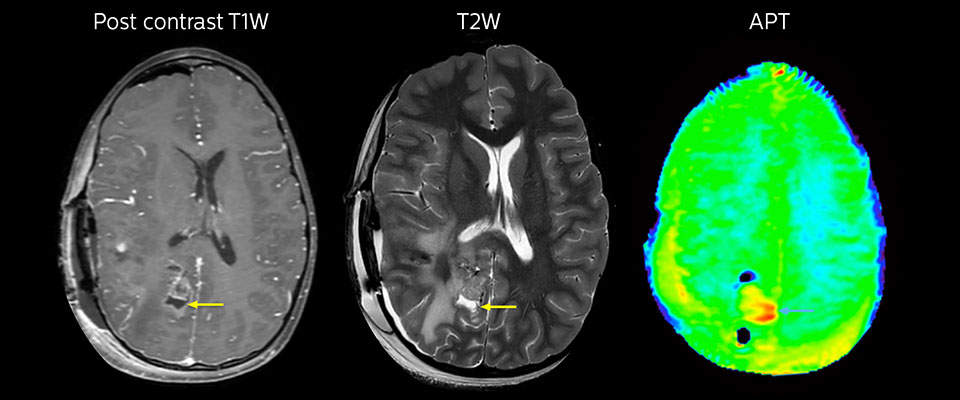

MRI may be performed after tumor resection, to look for residual tumor or tumor regrowth. Also here, the different contrast mechanism of APT may help in diagnosis. Dr. Miller remembers a particular case. “After a very good resection, we saw small changes on the postcontrast T1-weighted and the T2-weighted images that looked like a post-surgical little bit of fluid. Interestingly, however, we saw a focal area of APT signal, right in the center of that abnormality. As we usually do when a bit unsure, we followed it up and, unfortunately, found tumor regrowth in that region,” Dr. Miller says. “Cases like this motivate me, and others who care about this population, to investigate how this APT method could be used on large scale in this population and help us in providing high value diagnostic information.” The hospital’s physicians also saw a case where APT had a negative predictive value. Following the resection of a highgrade tumor, they saw a similar small change in the images of this patient. However in this case, the APT signal was rather low. In a recent rescanning of this patient, no recurrence was seen.

MRI with APT post resection

Immediately post resection MRI was again performed. T2-weighted and postcontrast T1-weighted images are quite inconclusive for distinguishing residual tumor tissue from postoperative tissue changes. On the APT image some high signal is still seen, which would suggest residual tumor tissue.

Follow-up over time

In later follow-up scans the post-contrast T1-weighted images suggest recurrent tumor growth. So, it would be interesting to study the predictive value of APT in a large patient group.